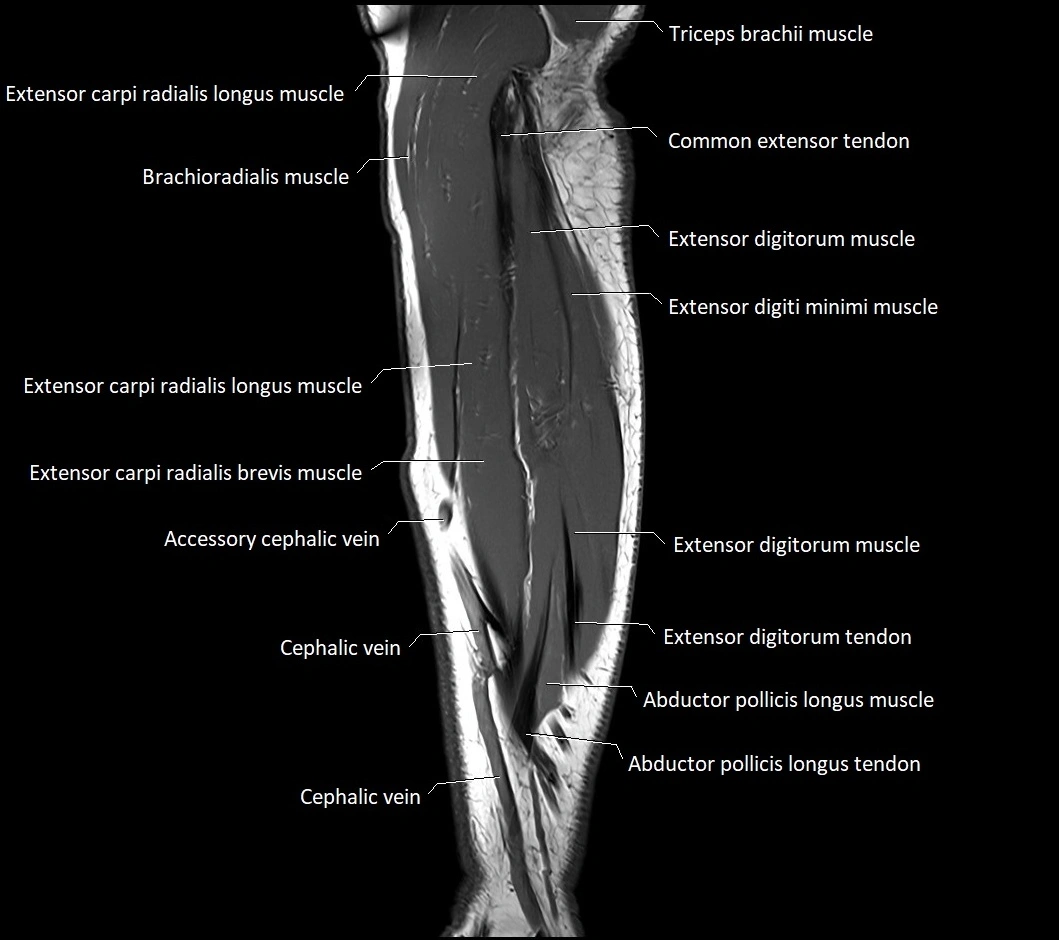

MRI images

image